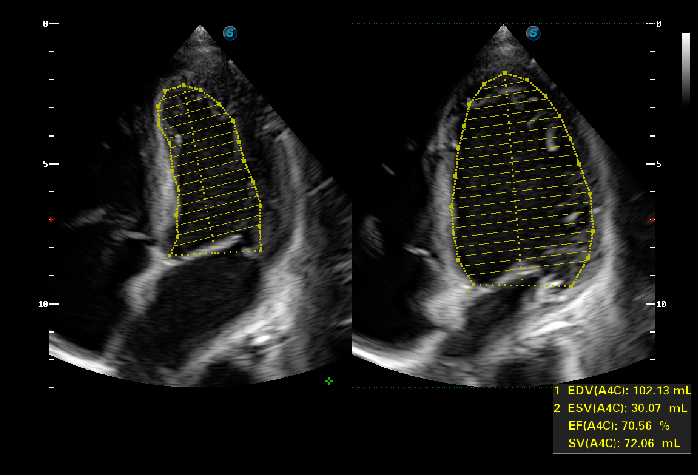

- Auto EF, auto IMT: tự động tính lưu lượng máu về tim

Để nhận biết nội mạc cơ tim trong giai đoạn tâm trương và tâm thu và tự động tính toán phân suất tống máu.